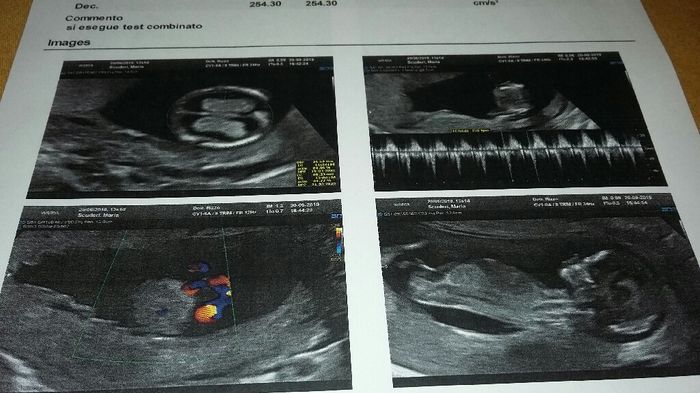

Ecografia translucenza nucale

Da Valentina , Il 6 Ottobre 2019 alle 13:13

Qualcuno riesce a capire il sesso......sono curiosa di sapere....